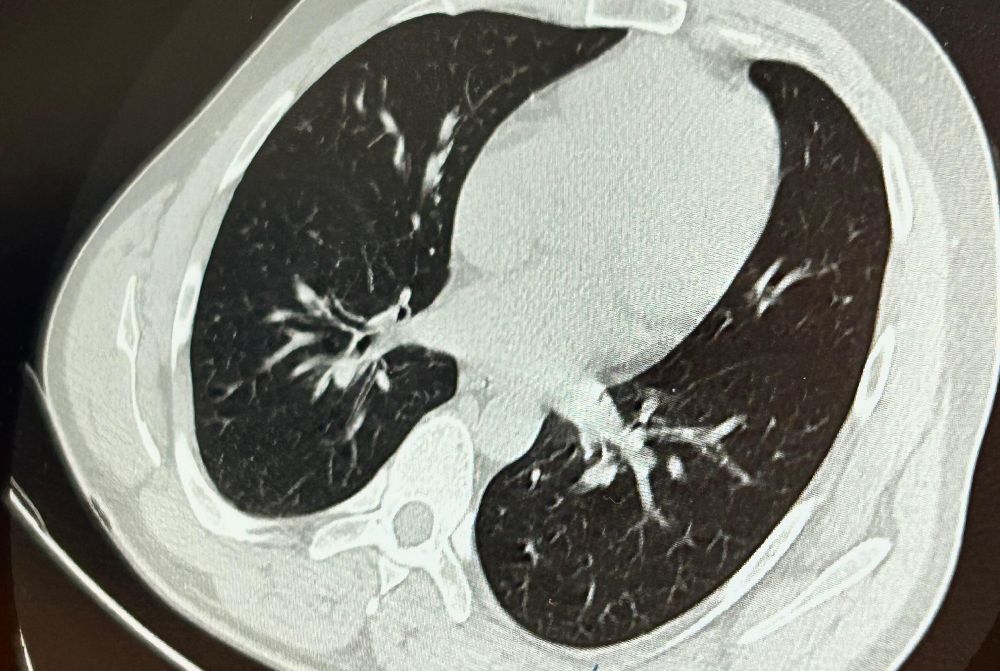

Konuya ilişkin konuşan Göğüs Cerrahi Op. Dr. Sadullah Aksoy, bir diş merkezinde diş tedavisi sırasında hastanın çenesine yerleştirilen implantın vida kısmının işlem esnasında yanlışlıkla aspire edildiğini belirtti. İlk olarak hastanenin ek hizmet binasında çekilen tomografi sonucunda, vidanın sol akciğerin hava yollarının yaklaşık dördüncü dalına kadar ilerlediği tespit edildiğini ifade eden Op. Dr. Aksoy, "Geçtiğimiz cumartesi günü öğle saatlerinde tarafımıza ulaşıldığında, hastanın Van Eğitim ve Araştırma Hastanesi'ne yönlendirilmesini istedik. Burada acil bronkoskopi planı yapılarak hasta kabul edildi. Hasta geldiğinde genel durumu iyiydi; solunumunu tamamen engelleyen bir bronş tıkanıklığı söz konusu değildi. Aynı gün hastamızı hazırladık. Bronkoskopi sırasında, implant vidasının sol üst lobun anterior segment bronşuna saplanmış pozisyonda olduğunu gördük. Üroloji bölümünde taş çıkarma işlemlerinde kullanılan cihazla müdahale ettik. İlk denemede implant tamamen çıkarılamadı ancak yerinden oynatılabildi. Bunun üzerine bir süre bekleyip hastayı yeniden bronkoskopi için hazırlamaya başladık. İşlem yaklaşık 3,5-4 saat sürdü ve saat 18.30 civarında hasta işlemden çıkarıldı" dedi.

Daha sonra hasta için yeniden bronkoskopi planladıklarını ancak bu süreçte hasta şiddetli bir öksürük geçirdiğini anlatan Aksoy, "Şiddetli öksürük sonrası yapılan kontrol akciğer filminde implant vidası görünmedi. Bunun üzerine toraks ve batın BT (bilgisayarlı tomografi) görüntülemesi istedik. Sonuçlarda implantın akciğerden çıktığı ve vücutta herhangi bir yerde bulunmadığı tespit edildi" diye konuştu.